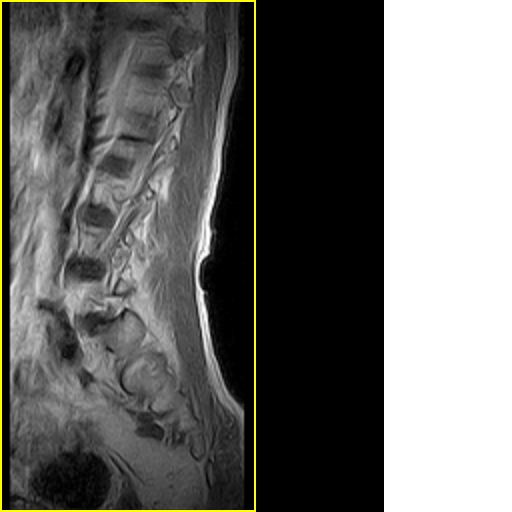

标题: MRI0859:[原创]腰椎,男,78岁,右下肢跛行两月 [打印本页]

标题: MRI0859:[原创]腰椎,男,78岁,右下肢跛行两月

男,78岁,右下肢跛行两月.

马尾神经炎

右侧黄韧带肥厚或钙化,压迫马尾神经所致。必要时行ct扫描。

退行性病变:增生、椎间盘变性、膨出[l4-5、l5-s1 椎间盘膨出]

我认为这一层面椎间盘应该合并左外侧型突出。

黄韧带肥厚.